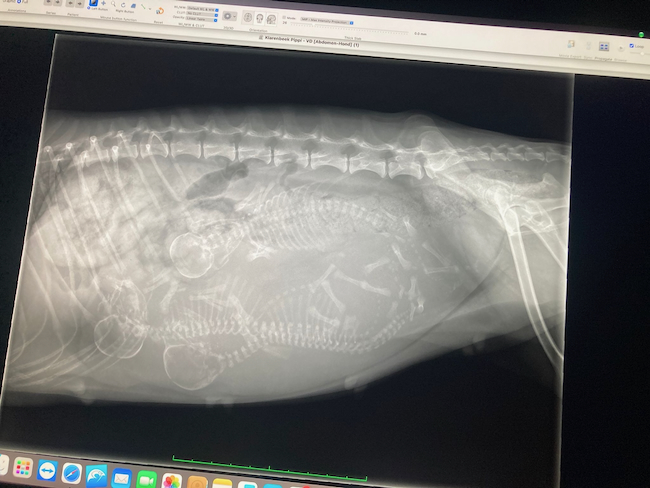

Op vrijdag 6 maart is Pippi bevallen van 3 mooie kleine teefjes. Er is 1 hele klein pup bij die elke dag groeit, maar drie keer zo langzaam als haar zusjes….

De bevalling verliep vlekkeloos en zeer snel. Mama was bij de eerste nog wat verbaasd, maar vanaf nummer twee nam haar moederinstinct het van haar over en leek het alsof het niet haar eerste nest was.